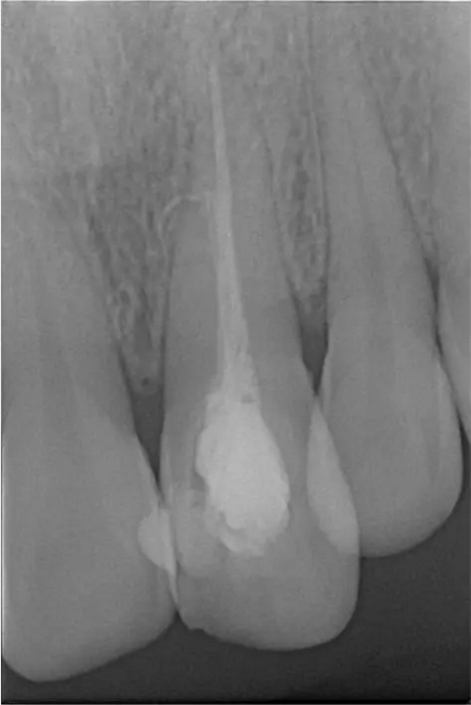

術(shù)前診斷片

患者女,年齡35左右,牙位21,根管治療曾經(jīng)歷過外院四到五次等不同地方的處理,還是不能咬硬物,會(huì)有酸、軟、痛的情況出現(xiàn),偶有自發(fā)疼痛,2016年9月初,轉(zhuǎn)診至我處治療21。術(shù)前拍片發(fā)現(xiàn)根中部存在側(cè)穿,橡皮障下常規(guī)再治療,隨后減輕了軟和痛的情況。因?yàn)閭?cè)穿,牙周膜受到牙膠尖等異物的持續(xù)刺激,酸軟的情況還是持續(xù)存在,所以決定行根尖外科手術(shù),采用MTA修補(bǔ)穿孔點(diǎn)。術(shù)后觀察半年左右,所有癥狀消除后,隨后熱牙膠充填。